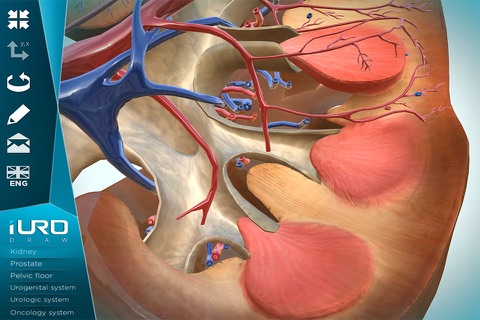

iURO Draw app for iPhone and iPad

Developer: URO Developments

Anatomical models on which to paint with different colors and to explain to patients and students various diseases and treatments.